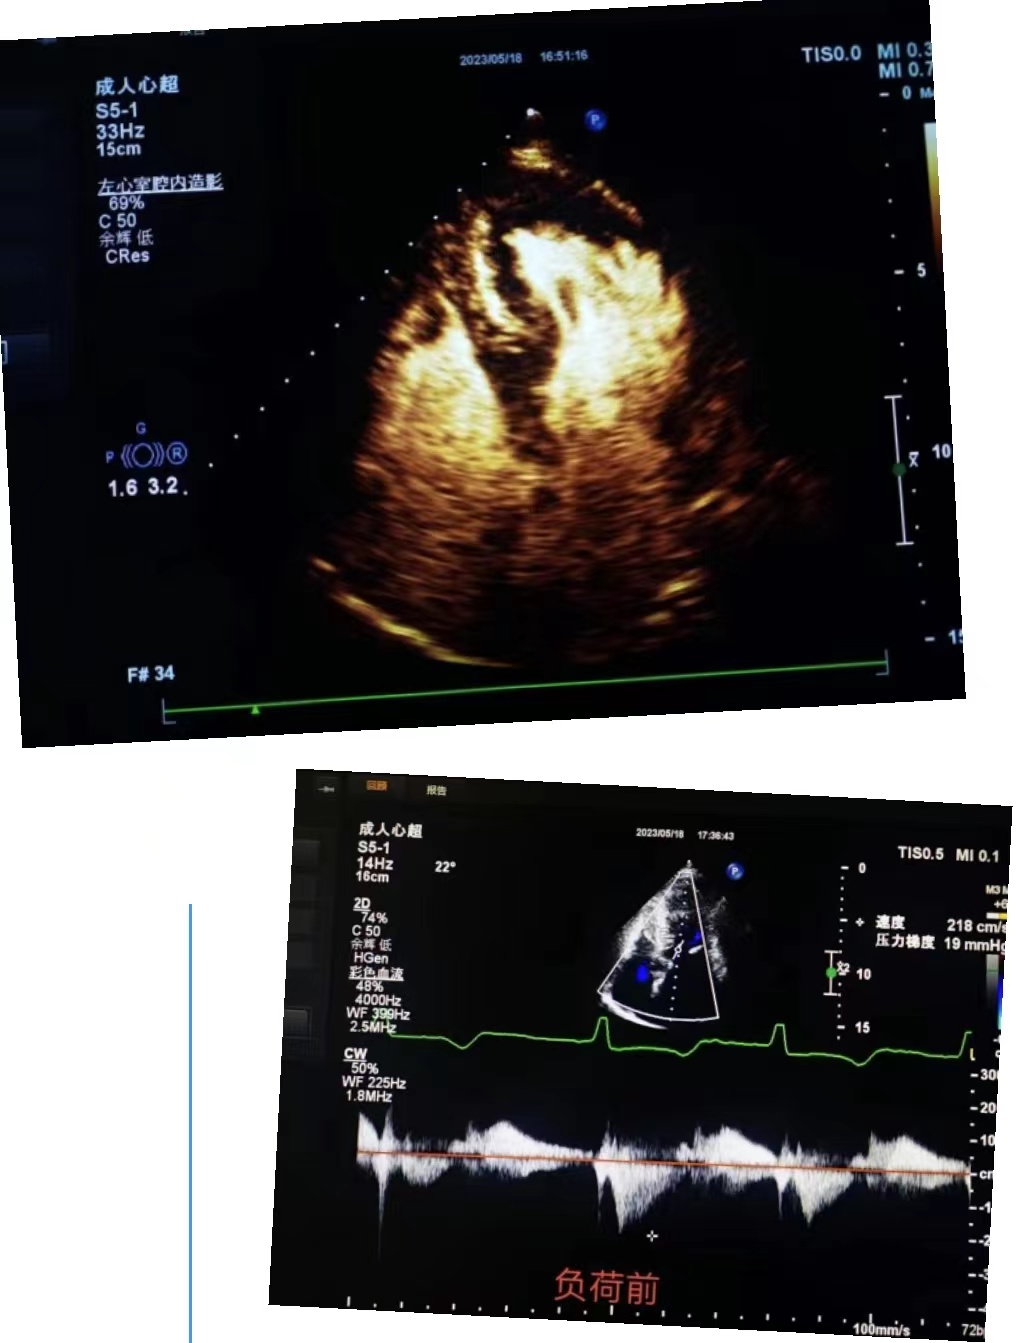

超声科王英莉主任及心血管组贾贝主治医师、陈辉主管护师及牛丹青护师为该患者行药物负荷超声心动图。监护仪、急救车到位,常规经胸超声心动图提示室间隔增厚,左室流出道血流速度略增快,左心腔超声造影,可清晰显示室壁显著增厚,符合肥厚型心肌病表现,随后又进行了多巴酚丁胺负荷超声心动图,静息状态下显示左室流出道血流速度V:207cm/s,PG:17mmHg;3分钟后心率达75次/分,左室流出道血流速度V:218cm/s,PG:19mmHg;6分钟后心率达94次/分,左室流出道血流速度V:386cm/s,PG:60mmHg;9分钟后达到目标心率,左室流出道血流速度V:649cm/s,PG:169mmHg,停止用药,药物负荷试验阳性,检查过程中患者无不适症状,最终诊断为隐匿性肥厚型梗阻性心肌病。